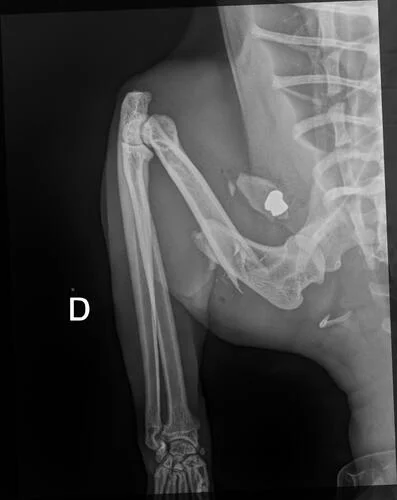

O gato Mimo, um dócil “laranjinha”, foi vítima de violência animal ao ser baleado pela segunda vez, sofrendo ferimentos graves que agora exigem uma cirurgia complexa para evitar a perda de um membro.O gato foi baleado em Cascavel, no Oeste do Paraná.

O exame de raio-x revelou que o ferimento não era uma queda, mas o gato foi baleado com projétil de arma de fogo. Alguém teria atirado no animal de forma intencional.

Mimo segue internado para estabilização e aguarda o procedimento cirúrgico para tentar recuperar o membro atingido.